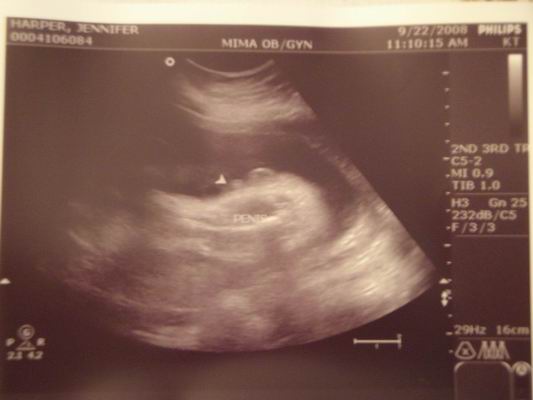

The picture below is from ultra sounds of the soon to be Harper due in December 2008. 9/22/2008 |

SUPRISE!!!....Yeah your reading that right we're expecting! I'm about 5 weeks pregnant. Due date is 12/16/08.

From Jennifer Harper.

4/29/2008